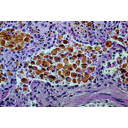

heart_failure_cells.jpg